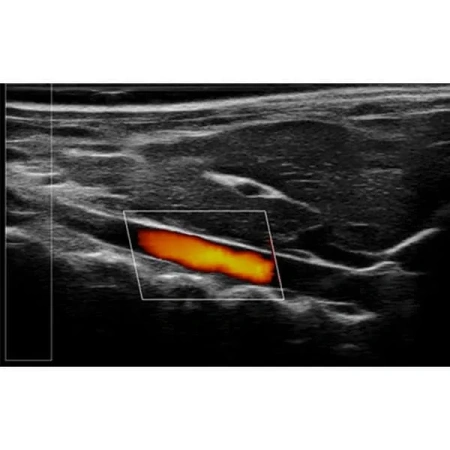

Благодаря неинвазивной и экономичной конструкции RevoSilex идеально подходит для повторных измерений в ходе долгосрочных исследований. Он обеспечивает точный мониторинг структуры, функции и гемодинамики сердца, что делает его незаменимым для исследований сердечно-сосудистых заболеваний и тестирования лекарств. Возможности цветного допплеровского картирования системы еще больше повышают ее полезность при оценке кровотока и выявлении ранних маркеров заболеваний.